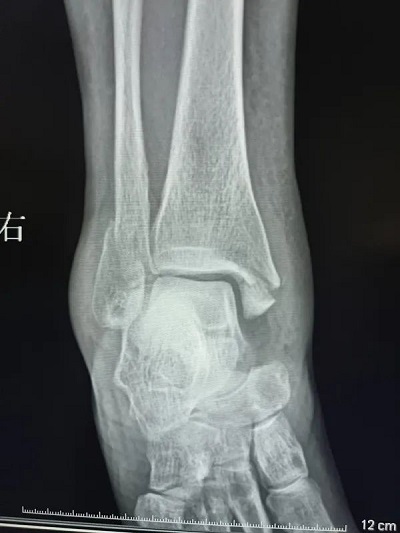

患者柯某某,女,58 岁,因外伤致右踝关节损伤,入院诊断为右内外踝骨折伴踝关节脱位,受伤后踝关节肿胀明显,给予系统性治疗,6天后消肿,手术前手足显微外科室多次讨论、综合评估、完善术前准备,制定了详细手术方案。由于担心自己年龄较大,患者不想二次进行手术取出金属内固定,选择可吸收钉板进行手术。在麻醉科的配合下用时近2小时左右顺利完成手术,术后拍片显示骨折及关节达到临床复位。

右内外踝骨折伴踝关节脱位术前